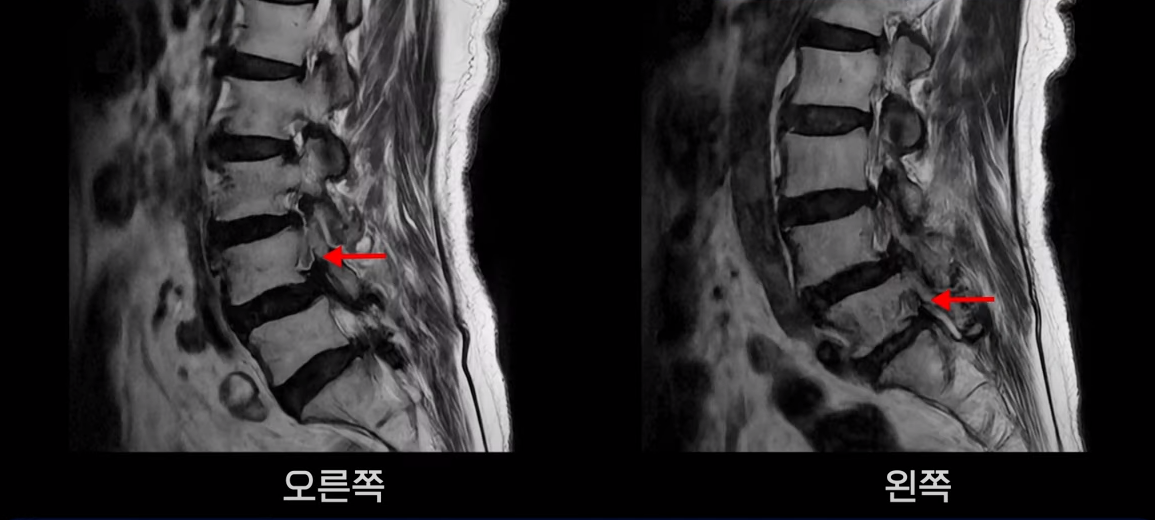

5번 1번도 척추관이 좁아져 있고 특히 좌우 신경이 빠져나가는 추간공이 좁아져 있는데 5번 1번 왼쪽 추간공은 많이 좁아져서 신경이 눌리고 있습니다.